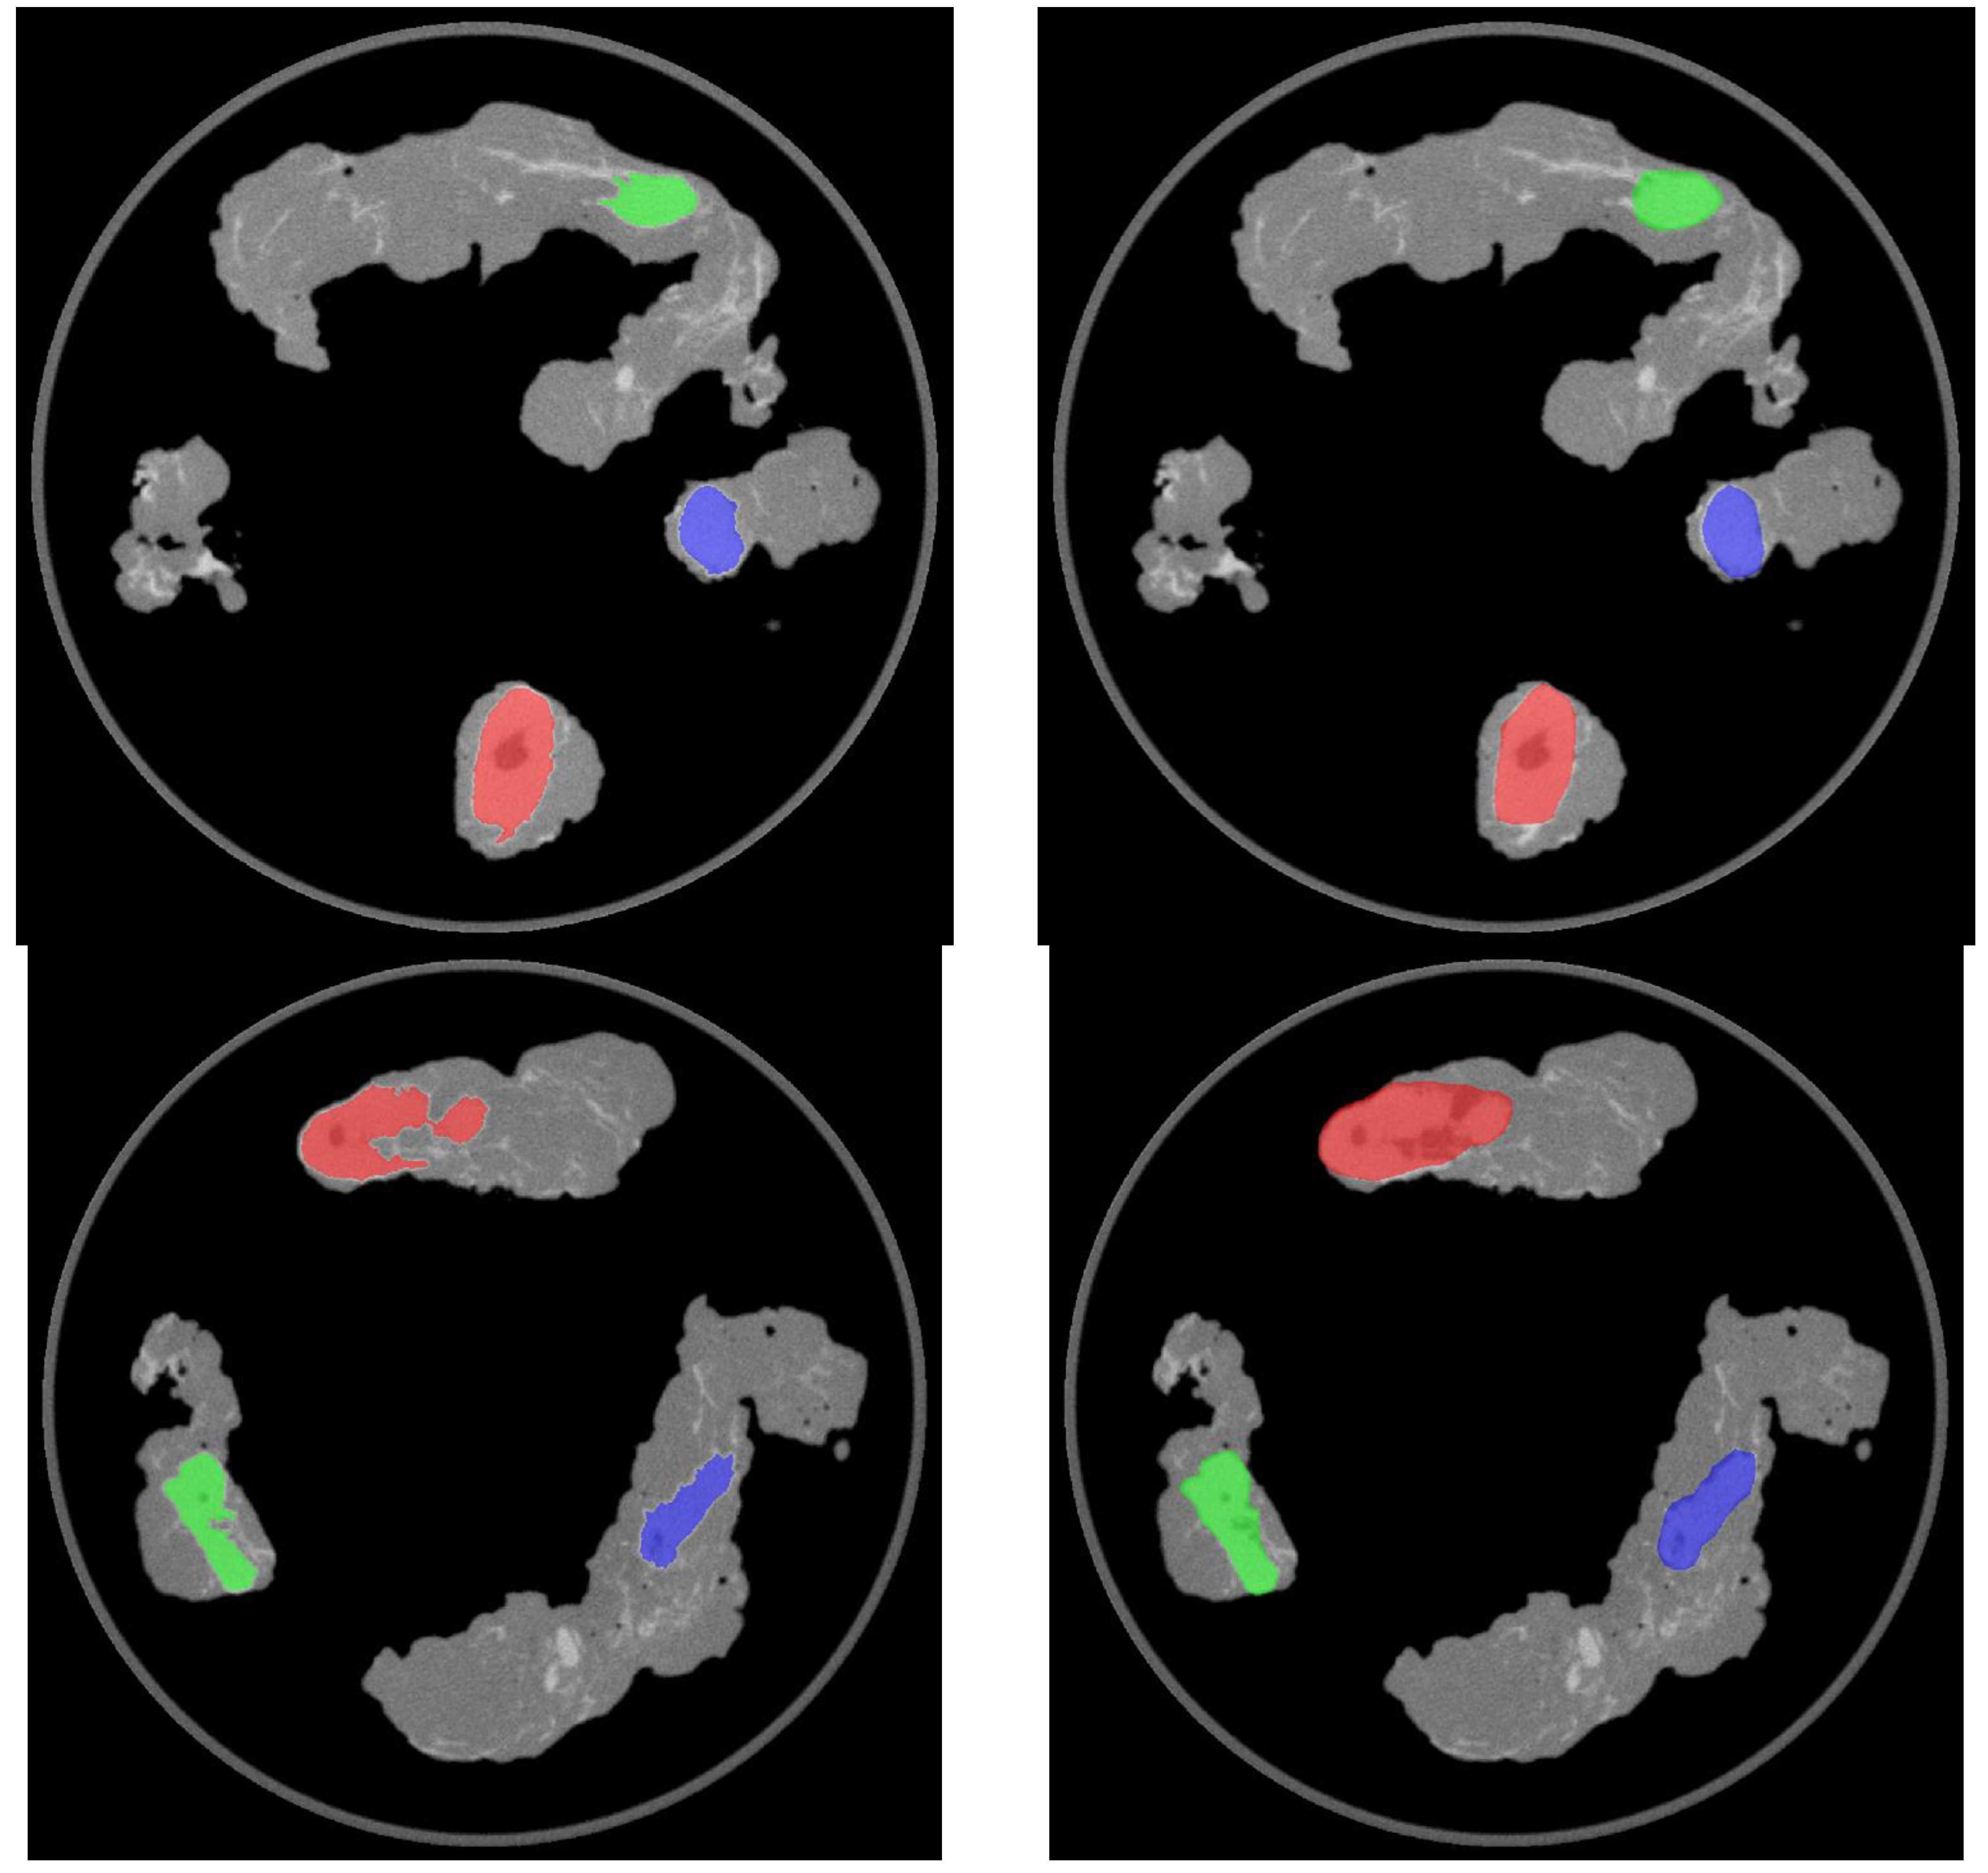

In the operating room, the acquisition of the specimens 68Ga-PSMA-11 PET/CT images with the intraoperative PET/CT scanner proved to be safe and feasible. The median time between radiotracer injection and specimen PET/CT imaging of the pelvic lymph nodes was 125 min. On average, the time required to complete the scanning process of a specimen case was 12 min. Figure 1a,b show the volume rendering of the PET/CT acquisitions, as well as two sample axial slices denoting mild tracer uptake in nodal structures.

Figure 1. (a) Volumetric rendering and axial view (b) of 68Ga-PSMA-11 PET/CT specimen images of the pelvic lymph nodes of a high-risk prostate cancer patient undergoing robot-assisted radical prostatectomy (RARP) and pelvic lymph node dissection (PLND). A, B: left obturator, C: left proximal external iliac, D: left distal external iliac, E: right distal external iliac, F: right obturator, G: right proximal external iliac.

Figure 4. Axial images showing the outcome of the automatic (left) and manual (right) segmentation of the 68Ga-PSMA-11 PET/CT nodal specimen images. Top row: left pelvic lymph nodes. Bottom row: right pelvic lymph nodes.